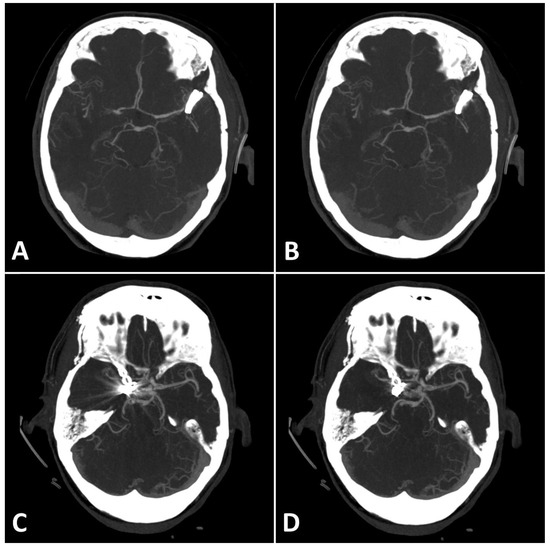

The first method comprised drawing five circular regions of interest (ROIs) with a radius of approximately (10 mm each) in both standard and SEMAR CTA images around the coil/clip mass in close vicinity to the foreign body and five other ROIs more distally from the foreign body in a similar manner to previous reports [8,9,13], while focusing on the artifacts and avoiding the metallic mass, air, and bones (Figure 1). The ROI settings were constant between standard and SEMAR images. The mean density and standard deviation (SD) of each five of the five ROIs were measured in HU (Hounsfield–Units). The average image noise within the ROIs was set as the standard deviation and was considered as an index for the metal artifacts.

Figure 1.

Positioning of ROIs (Region of Interest) for quantitative image analyses on standard (A) and SEMAR (B) CT-angiography images in axial plane (0.25 mm slice thickness) in direct proximity and more distally to the metal implant. In this case, follow up CT-angiography of a 56-year-old female who underwent coil-embolization of a left sided posterior communicating artery aneurysm.